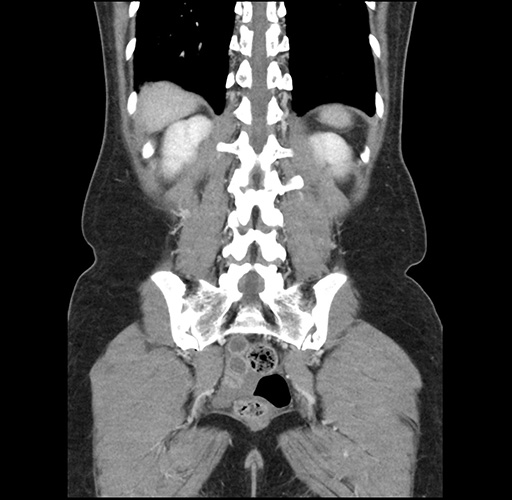

Left lateral sectionectomy [case 12]

Imaging Analysis

Look through the patient's CT scan to identify any areas of concern for the necessary procedure.

Based on your CT findings, which issue(s) would give reason for "planned slowing down moment(s)" in this case?

Considering a standard left lateral sectionectomy procedure, what step(s) of the operation would you do differently in this case ?